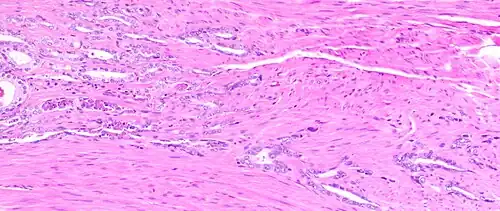

The prostate consists of glandular and connective tissue.[2] Tall column-shaped cells form the lining (the epithelium) of the glands.[2] These form one layer or may be pseudostratified.[4] The epithelium is highly variable and areas of low cuboidal or flat cells can also be present, with transitional epithelium in the outer regions of the longer ducts.[10] Basal cells surround the luminal epithelial cells in benign glands. The glands are formed as many follicles, which drain into canals and subsequently 12–20 main ducts, These in turn drain into the urethra as it passes through the prostate.[4] There are also a small amount of flat cells, which sit next to the basement membranes of glands, and act as stem cells.[2]

The connective tissue of the prostate is made up of fibrous tissue and smooth muscle.[2] The fibrous tissue separates the gland into lobules.[2] It also sits between the glands and is composed of randomly orientated smooth-muscle bundles that are continuous with the bladder.[11]

Histology of normal prostate, H&E stain, with benign features: Glands are rounded to irregularly branching, with an inner layer of epithelial cells surrounded by an outer layer of basal cells. They are surrounded by ample stroma. -

Histology of prostate with gradually increasing simple atrophy from left to right, H&E stain. Crowding and angulation may mimic that of adenocarcinoma, but there is nuclear basophilia rather than atypia, and occasional basal cells can still be seen.